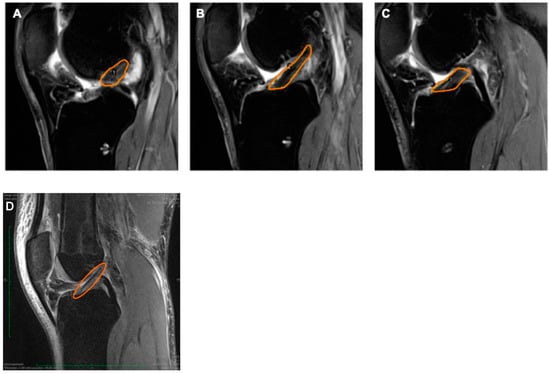

3.3. Radiographic Evaluation